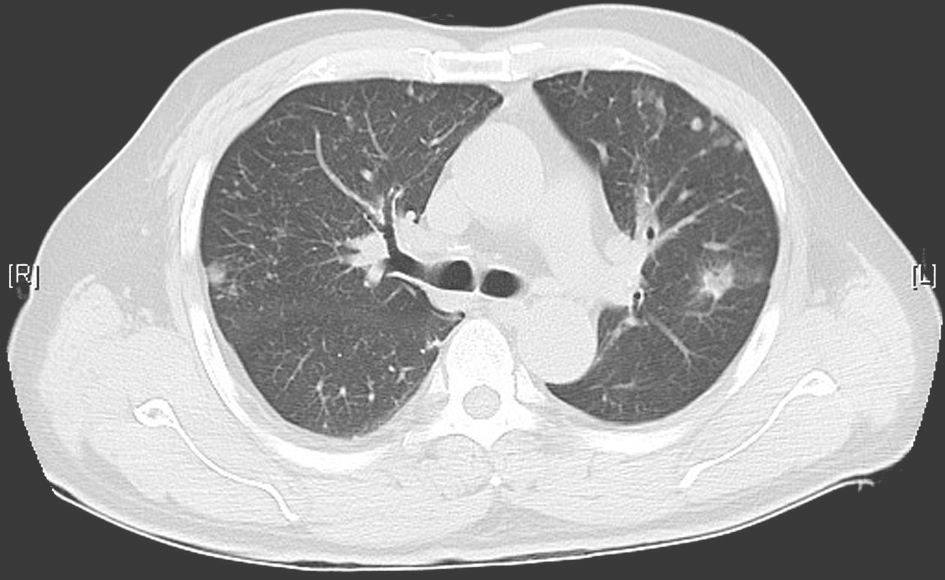

(1)胸部CT(外院)

可见双肺以肺门为中心的弥漫性磨玻璃样渗出影,累及叶间裂(图1)。

图1 胸部CT表现

胸部CT示双肺弥漫磨玻璃样渗出影,主要以肺门为中心分布。肺功能检查提示弥散功能减退,限制性通气功能障碍。支气管镜下所见及病理检查结果提示感染。BALF培养出恶臭假单胞菌。